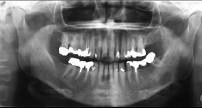

黏液表皮样癌(如组图)以下哪种说法不正确 ( )

A低分化者常见颈淋巴转移

B高分化者少见颈淋巴结转移

C一般分为高分化和低分化两类

D各型治疗原则相同

E多发生在腮腺